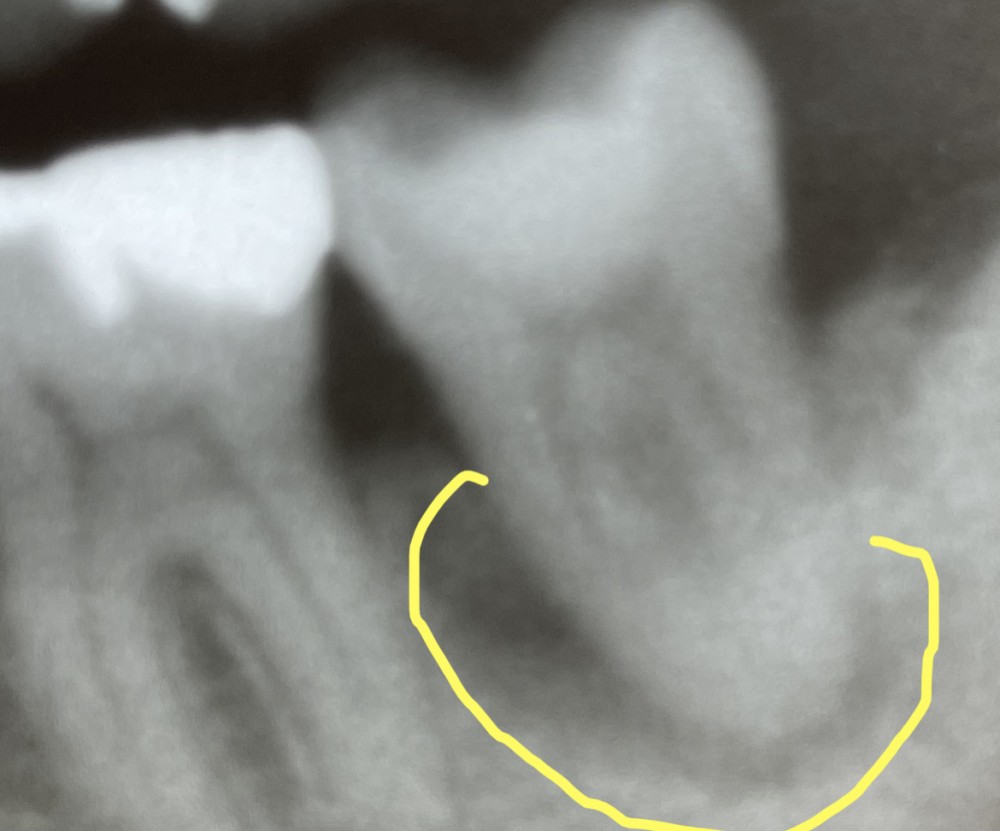

上のエックス線写真では、左下第二大臼歯の周囲の歯槽骨の炎症が疑われます。

下の写真は、上と同じもので、歯槽骨の病巣が疑われる部分を黄色く囲みました。